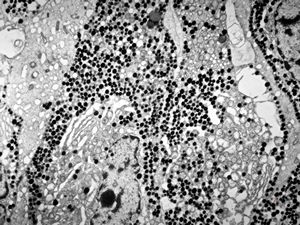

M, 38y. | pheochromocytoma